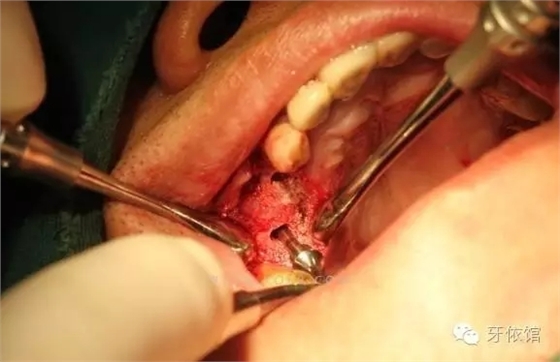

兩個(gè)洞內(nèi)分別放入適量骨粉。

將骨粉在竇膜下均勻攤開。

根據(jù)需要植入的植體的規(guī)格用擴(kuò)孔鉆擴(kuò)孔(此時(shí)因?yàn)橛泄欠鄣谋Wo(hù),一般不會(huì)將膜刺破)。

植入更多的骨粉。

植入植體。

植體的平行度很好

深度也很滿意。

縫合。

術(shù)后X光片